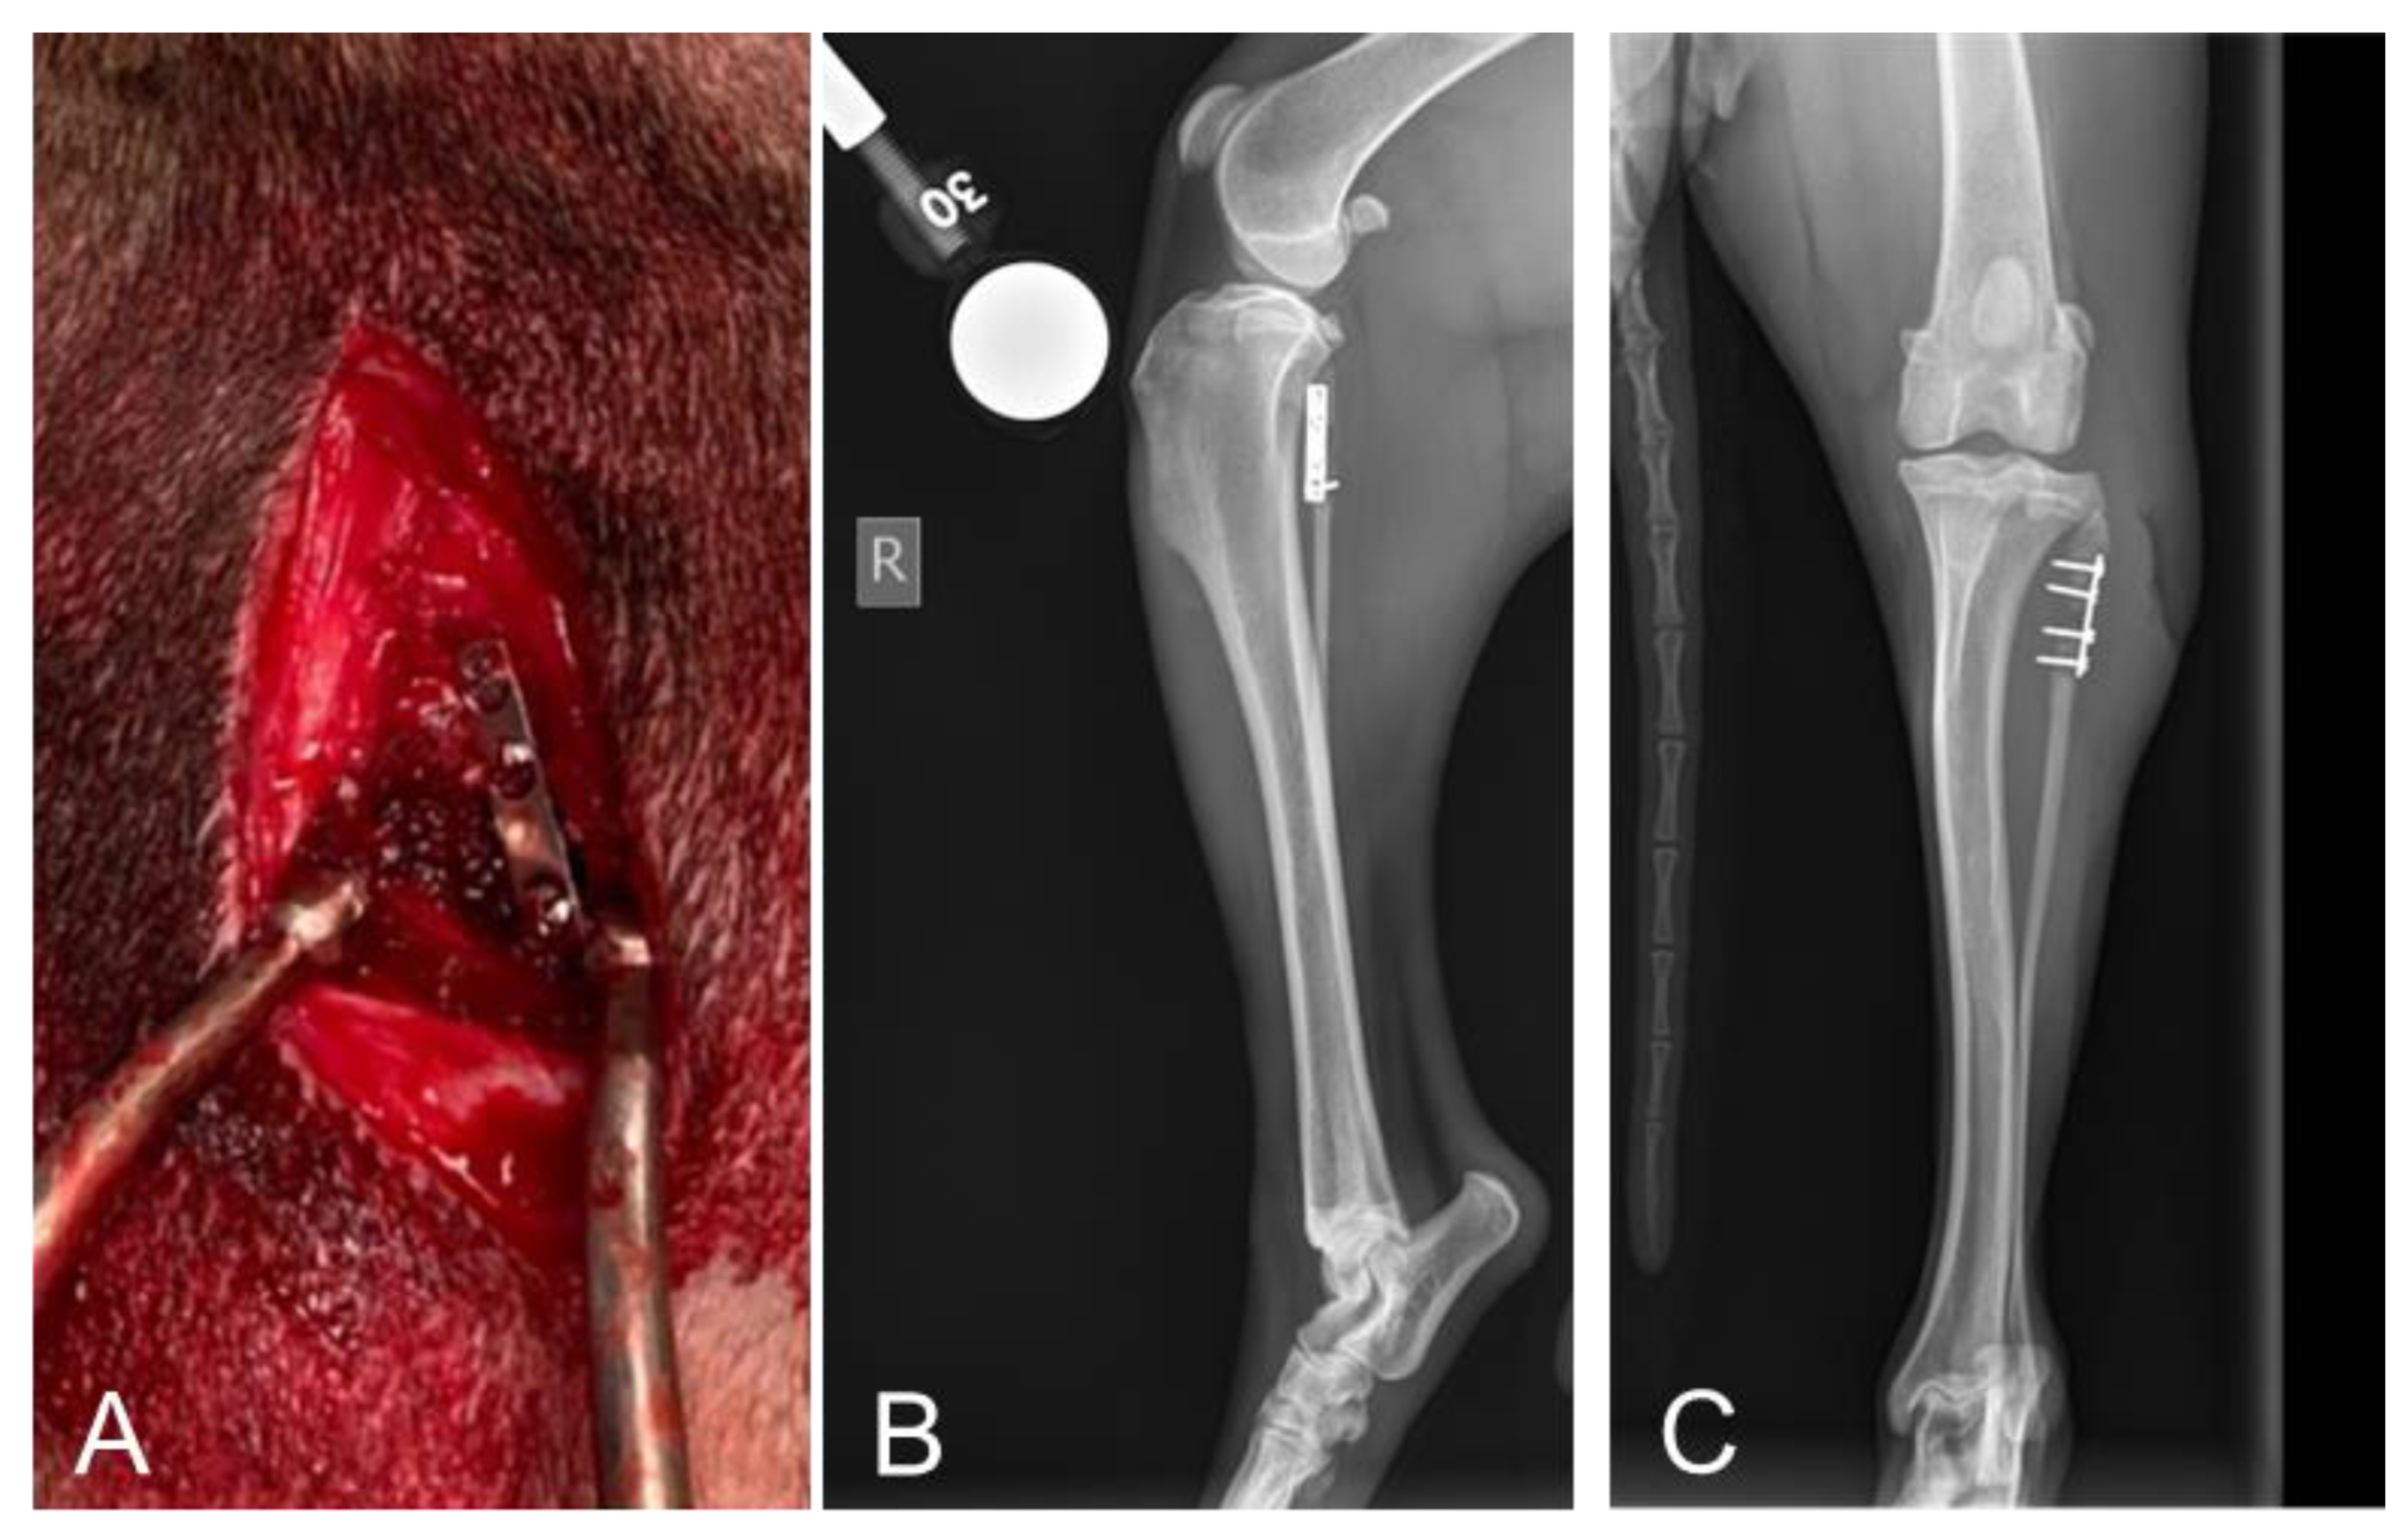

2.2. Radiographic Assessments Revealed No Implant Failures Following 10 Days of Treatment

4.5.1. Radiographic Evaluation